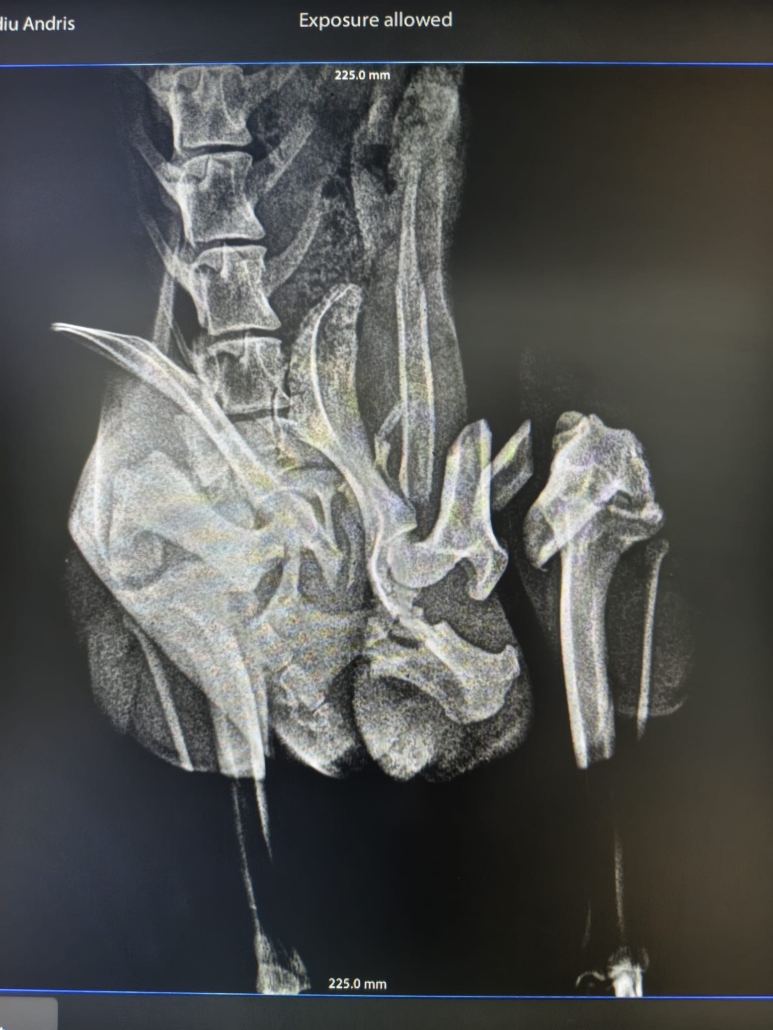

leider war sein Name durch den Umstand entstanden, dass er verletzt (vermutlich durch einen Unfall) auf der Straße gefunden wurde….

Wie lange er schon mit dieser Verletzung unterwegs war…. wir wissen es nicht… auch über sein bisheriges Leben können wir nichts sagen…

Er hat die OP gut überstanden und darf sich noch ein bisschen in der Tierarztpraxis erholen… doch dann braucht er einen sicheren Platz um wieder vollkommen zu genesen…. Leider ist es fast unmöglich vor Ort eine Pflegestelle zu finden… 🙁 und die Finderin, die sich aktuell um ihn kümmert, verlässt im März Rumänien…